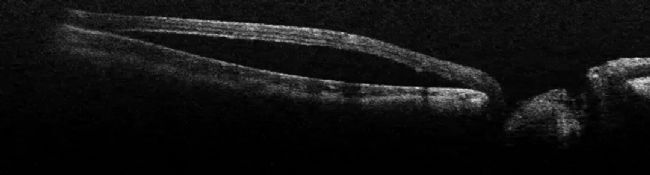

一名年輕女孩出現(xiàn)視盤凹陷。術(shù)中 OCT 顯示視盤旁邊的視網(wǎng)膜被擠出,中心凹脫離(圖 13)。為了治療患者,醫(yī)生對其進(jìn)行了玻璃體手術(shù)。玻璃體被剝離,視網(wǎng)膜被稍微抬起。術(shù)中 OCT 控制了整個操作過程,避免了過大的壓力(圖 14)。

圖 13:術(shù)中 OCT 顯示視盤旁邊的視網(wǎng)膜被擠壓,中心凹脫離。圖片由 Nikolaos Bechrakis 教授提供。

圖 14:玻璃體脫離,視網(wǎng)膜被稍微抬起。圖片由 Nikolaos Bechrakis 教授提供。

這次手術(shù)的計劃是進(jìn)行內(nèi)界膜(ILM)剝離。在注射了內(nèi)層緣膜染料后,用 25g 儀器剝離了內(nèi)層緣膜(圖 15)。使用改良的黃斑孔倒置內(nèi)膜瓣技術(shù)后,液體進(jìn)入視網(wǎng)膜和視網(wǎng)膜下方的區(qū)域被密封。術(shù)中通過 OCT 確認(rèn)了 ILM 的適當(dāng)位置。術(shù)后,積液慢慢減少,視力也有所提高。